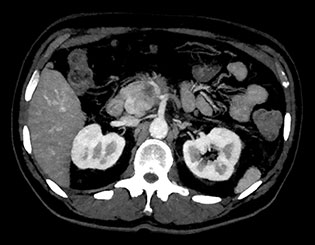

Здесь представлена серия изображений, на которых значения воксела обозначают эффективное атомное число. Эффективное атомное число может быть дробным, обозначающим какой-либо элемент, соединение или смесь. Данное число может отличаться от порядкового номера, указанного в периодической таблице. Единица для обозначения — Z.